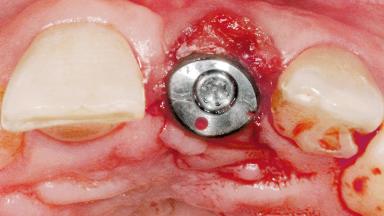

Late Flapless Placement of an Implant in a Maxillary Left Central Incisor Site

Type of Implants One-Piece

Attachment One-Piece

Soft Tissue Grafting Simultaneous